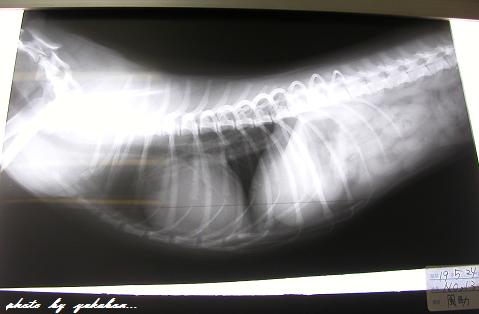

直ぐに血液検査・レントゲン撮影。

そうこうしているうち、少しずつ舌の色もピンク色に

しかし、血液検査では肝臓の数値が普通の3倍。

レントゲンでは、肝臓が小さめで心臓が少し大きいと。

肝臓小・心臓大。

先生曰く、ガムを飲み込んだのでは無く、

《発作》を起こしたと考えられるそうです。